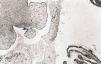

Mujer de treinta años de edad que consulta por hernia inguinal izquierda de seis años de evolución, solicitando asimismo esterilización voluntaria, practicándosele herniorrafia de reducción y salpinguectomía parcial bilateral laparoscópica, observándose una masa quística paratubárica de 3 cm de diámetro a nivel del segmento distal de la trompa izquierda (Fig. 1), la cual fue extirpada.

Figura 1.Papilas tumorales del cistoadenofibroma en relación con la porción fímbrica tubárica (H & E, x 25).